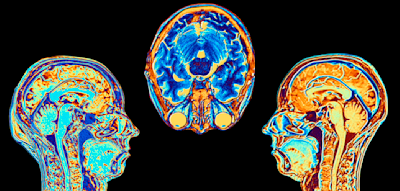

Nach Angaben seines Teams Nu Colombia wurde Muñoz nach dem Unfall zunächst wegen einer Knieverletzung behandelt und anschließend in eine Klinik im nordspanischen Oviedo verlegt. Dort wurde eine schwer zu kontrollierende Infektion festgestellt – trotz medizinischer Versorgung verschlechterte sich sein Zustand, und es kam zu Komplikationen, an denen er schließlich starb.